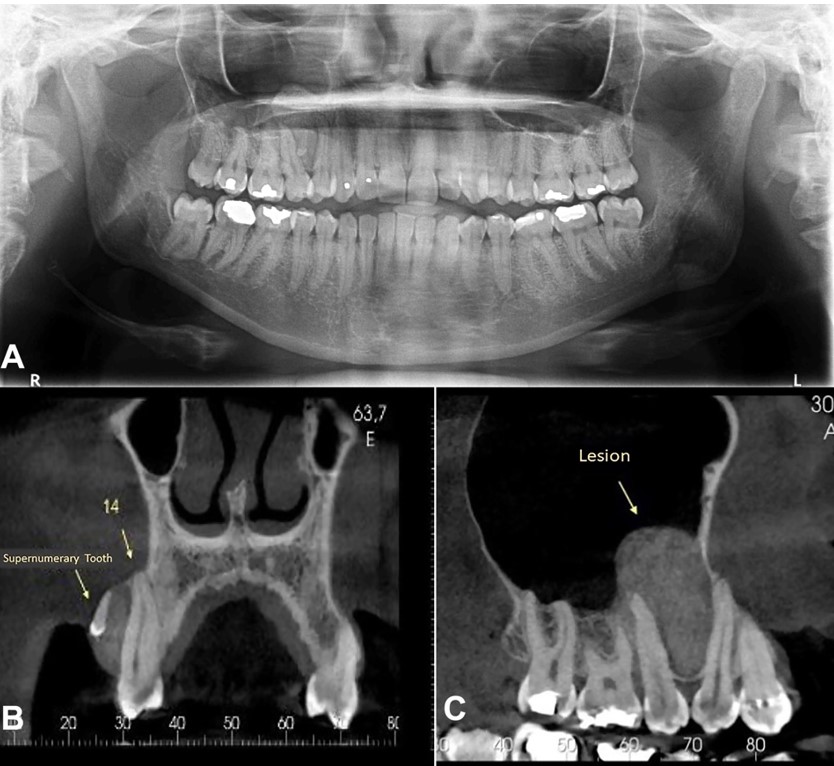

Panoramic radiography revealed a unilocular lesion surrounding a mineralized structure that resembled a denticle between the roots of the first and second right upper premolars (Figure 2A). Cone-beam computed tomography (CBCT) revealed expansive lesion growth into the maxillary sinus that caused the displacement of first and second right upper premolar extending to the upper right first molar. In addition, an impacted supernumerary tooth associated with the lesion was observed (Figure 2B-C). The diagnostic hypotheses were CEOT and central ossifying fibroma, and the patient was thus submitted to an incisional biopsy.